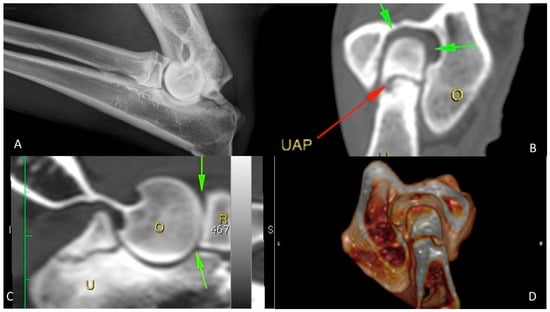

3.4. Follow-Up

The first control was performed at three weeks after treatment: dogs did not show any local or systemic adverse reactions, such as infections, swelling or leaking from the injection site. The clinical examination showed a progressive reduction in pain within 3 weeks after BMMC administration upon gradually increased weight bearing on the affected limb. The carpus valgus attitude was still appreciated. A progressive reabsorption of synovial fluid resulted in a reduction in joint effusion to a complete remission of clinical signs at 3 months post stem cell injection. The radiographic and computed tomography examinations, performed at 21, 90, 180, and 270 days after the treatment, revealed progressive fusion of the ossification centre, which was completed at 90 days without any signs of secondary OA after 270 days follow-up (Figure 3).

Figure 3.

German shepherd female, 7 months old; grade 2 UAP. (A–D) Preoperative X-ray and CT exams; (E–G) post-operative control at 60 days; (H–J) post-operative control at 270 days. The arrows underline the anconeal process reparation. The O stands for humerus and the U stands for ulna.